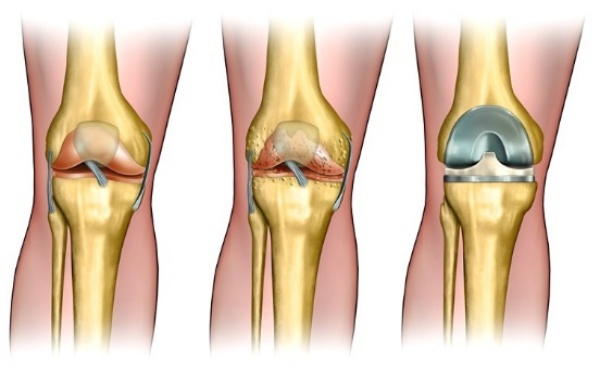

관절염 개선

우리 체내의 뼈를 구성하는 연골이 있다. 그 연골은 나이가 먹음에 따라 점차적으로 감소 하는데, 그 감소하는 역할인 단백분해효소를 직접적으로 감소함으로 관절건강 유지를 하는데 보스웰리아 효능이 발휘한다고 한다.

한 연구자료를 예로 들면, 실제 미국에서 관절염 개선에 대한 내성 연구를 진행하였는데, 보스웰리아를 먹은 그룹은 무릎 통증이 아주 많이 감소했고, 움직임 개선, 관절 붓기 감소와 같은 효과가 나타났다고 한다.

이처럼 관절염 연구 결과에 따르면, 보스웰리아 추출물은 관절염에 효능이 있음을 보여준다. 통증과 부기를 완화하는 등 관절염 개선 효과가 상당하다고 하여, 많은 이들이 이미 찾기 시작하는 제품중 하나이다. 관절염은 특별한 요인이 없더라도 노화 과정에서 누구나 겪게 되는 질병이기 때문에 미리 준비해두고, 관절염에 좋은 성분이 풍부하게 들어 있는 보스웰리아 식품으로 그 증상을 완화할 수 있을 것이다.